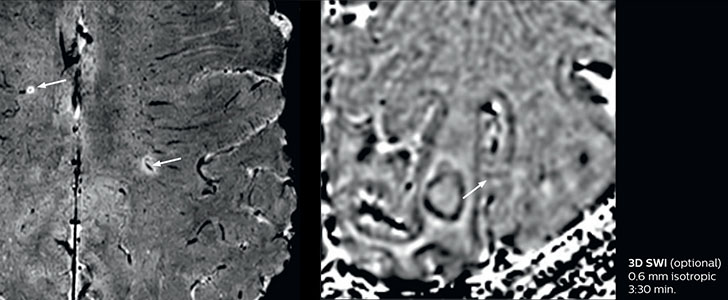

Giant cell arteritis

The 3D TSE T1w black blood MSDE sequence with fat suppression has an isotropic 0.8 mm voxel size and sagittal oblique and axial reformats are made. The images show superficial temporal artery thickening and peri-arterial fat infiltration. The 3D TSE PDw black blood MSDE with fat suppression has 0.55 mm isotropic voxels. The images shows focal involvement of the frontal branch of the superficial temporal artery.